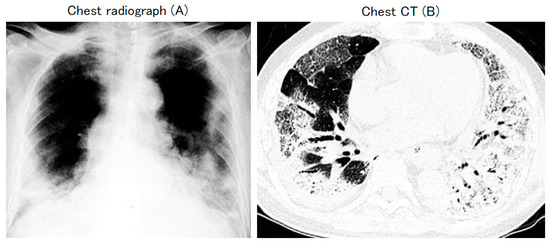

The patient was a middle-aged woman with underlying breast cancer and poor liver function due to fatty liver. She was undergoing hormone therapy. Despite this, she was in good general health and even rode her bicycle under the scorching sun during the hot summer season. However, CT revealed a clear image of pneumonia (Figure 2). This circular infiltrate shadow is often called the marimo sign in Japan because it resembled the marimo (a type of freshwater green alga named for its ability to form spherical aggregates) found in Lake Akan, Hokkaido, Japan. The patient was hospitalized but did not require any specific treatment, and at the 3-month follow-up, the pneumonia disappeared.

Figure 2.

Chest CT of case 2: 47-year-old female.

This case was clinically COVID-19 although repeated PCR test results were negative because the chest CT showed a clear image of pneumonia and a clear family history of infection was present (Figure 3).

Figure 3.

Chest CT of case 2: 55-year-old female.

The patient was clinically thought to have COVID-19; however, as a definitive diagnosis could not be made through PCR testing, the patient was followed-up without hospitalization and without specific treatment, and at the 2-month follow-up, the pneumonia on the CT image disappeared (Figure 3). This case is educational and demonstrates that false-negative PCR tests do occur.